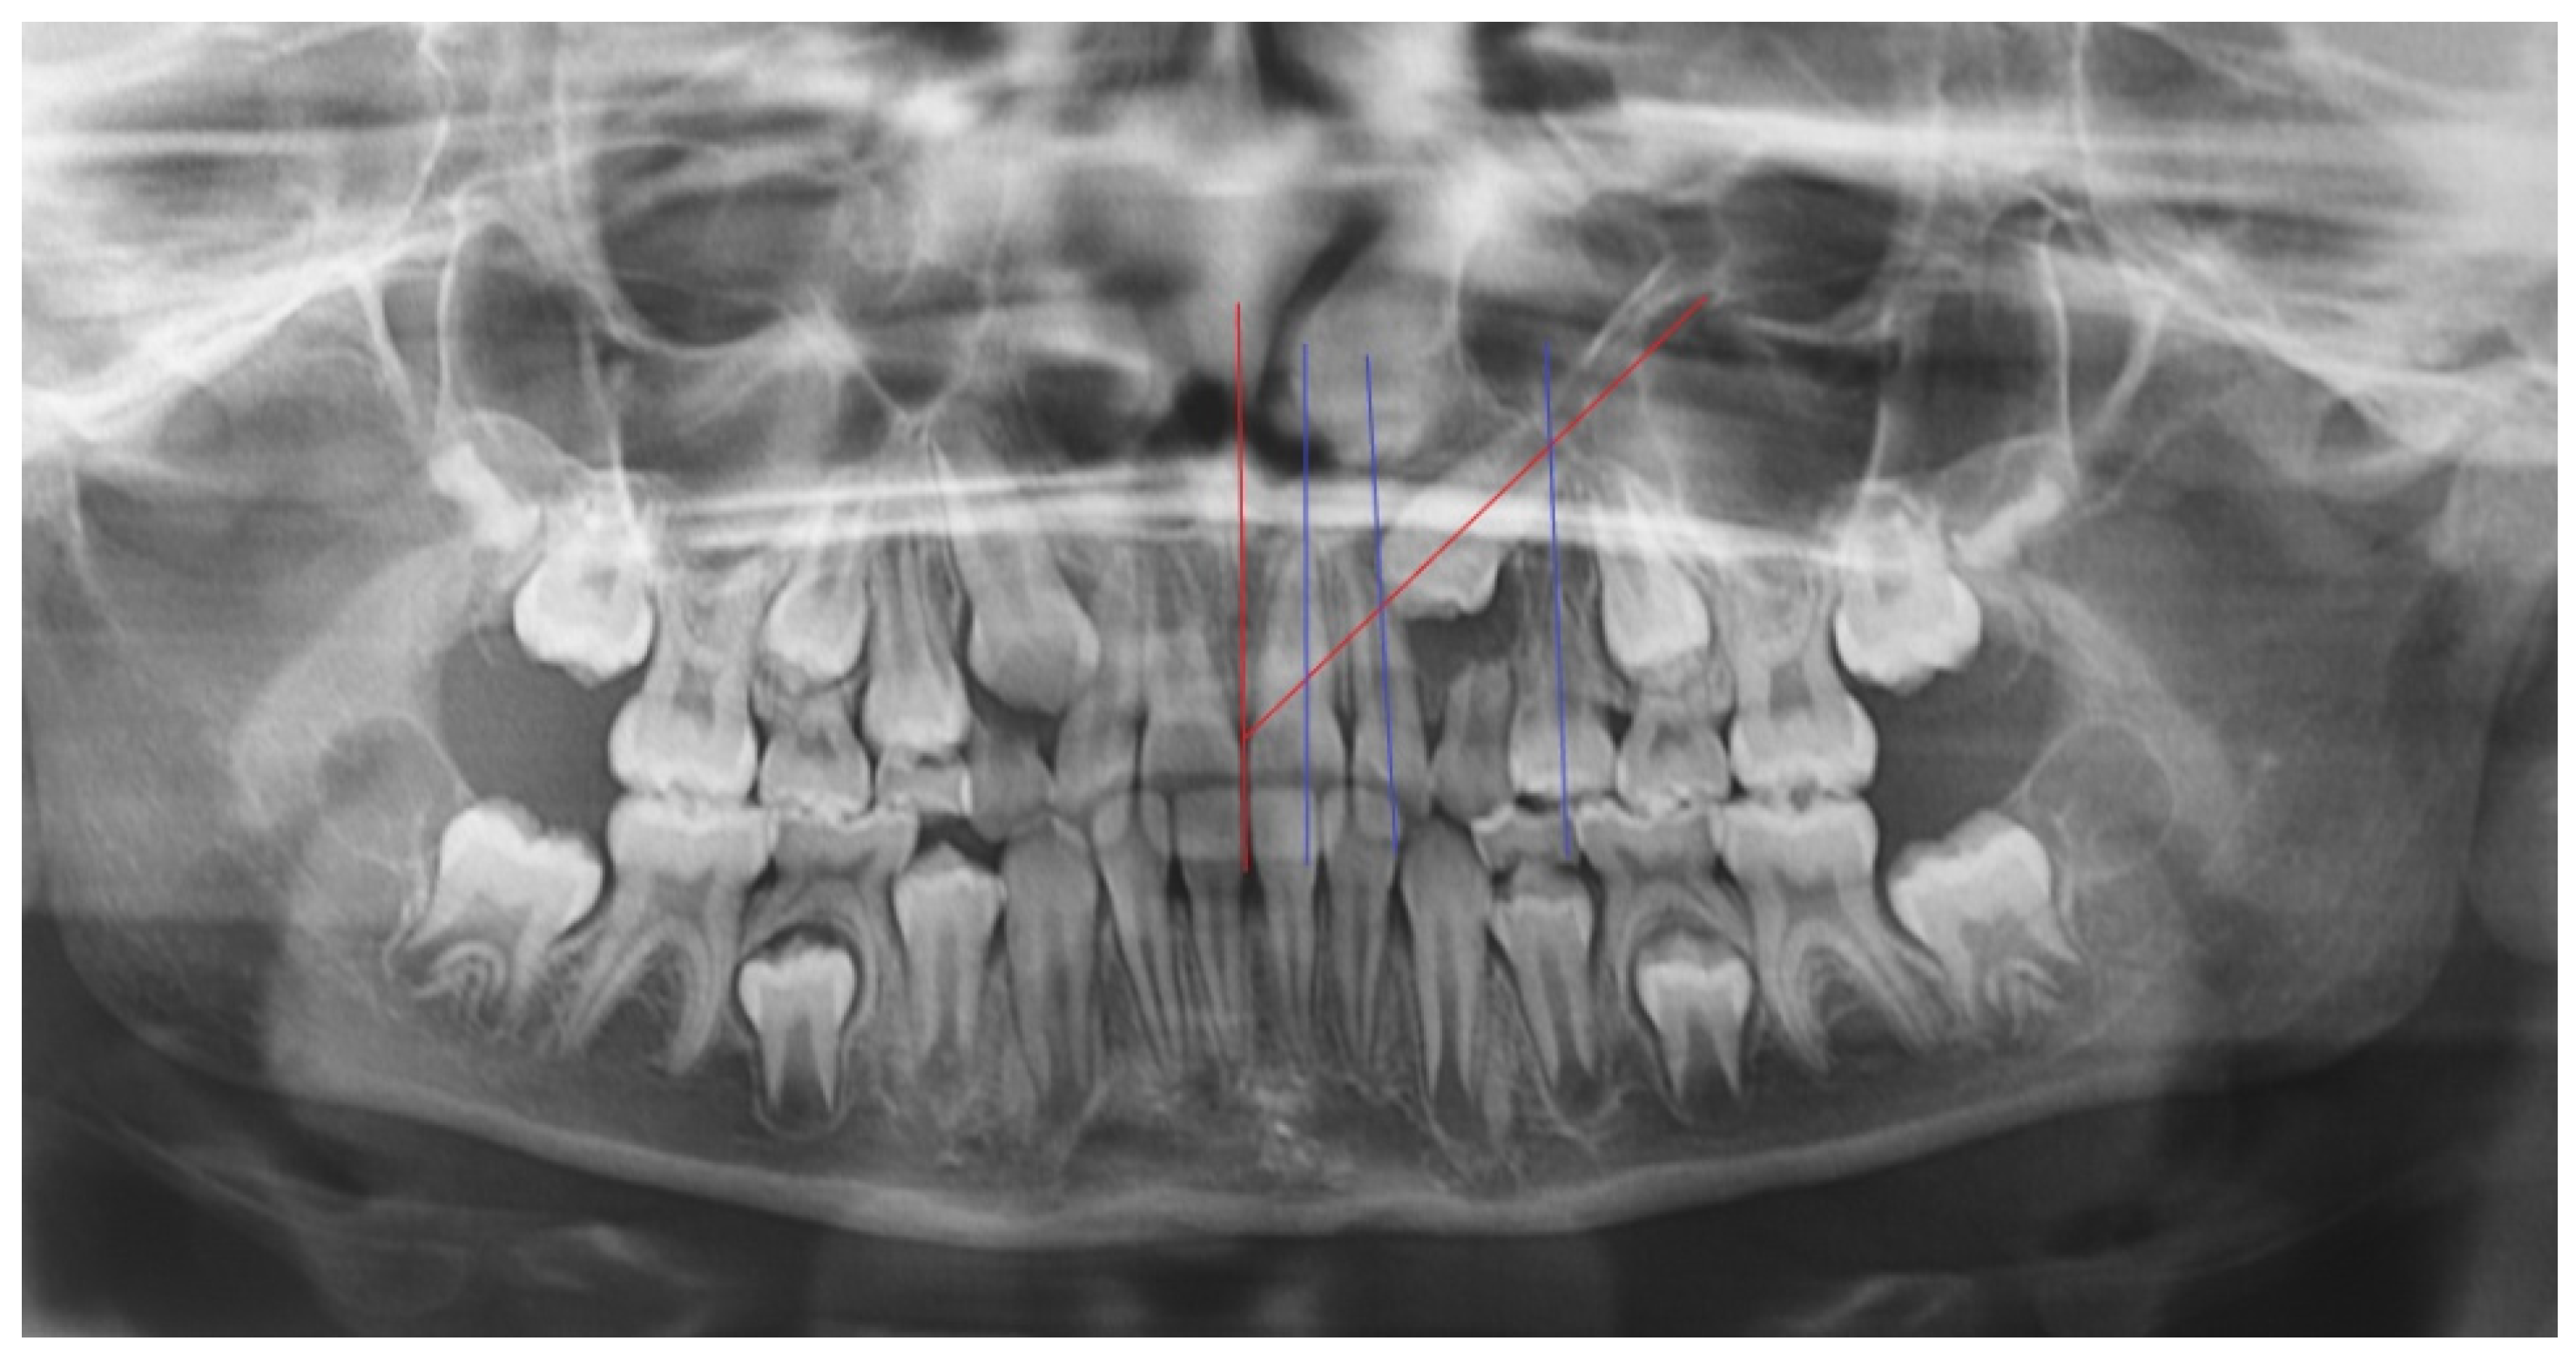

- In the first step, a panoramic radiograph and a teleradiography of the skull in latero-lateral projection is required. The observation of the panoramic radiography should show the position of the impacted canine, evaluating the relationships of the canine crown with the roots of the adjacent teeth, the alpha angle, and the distance of the impacted tooth from the occlusal plane. The cephalometric study of the teleradiography should provide information about the eventually present malocclusion and treatment needed;

- Mesioinclinated Canine in Close Relation to The Root of The Lateral Incisor: In cases of vestibular canine impaction, a tight relation between the canine crown and the lateral incisor root is often visible. Every so often, moreover, the lateral incisor presents with a horizontal displacement due to the pressure of the erupting mispositioned canine. This condition frequently correlates with an increased risk of root resorption for the lateral and sometimes also for the central incisor. An orthodontic force applied on the canine crown and directed with a distal and occlusal vector could increase the probability of pressure, due to the fact of this latter component, and could therefore increase the risk of root resorption. Conventional treatment should provide a traction arm in a high position and with a horizontal force direction, thus increasing the patient’s discomfort and the likelihood of eruption in free mucosa. Complex and multidisciplinary cases are particularly prone to this difficult operating condition with wide areas of contact between roots and crowns of impacted teeth [24,25]. In any case, a previous evaluation of the disimpaction prognosis is mandatory (angulation, better if the impacted tooth is mesio-angled, α angle, and sector S of localization of the crown according to the classification of Ericson and Kuroll modified by Baccetti [22]).

- Adequate/Inadequate Interadicular Space for The Insertion of The Miniscrew: The positioning of TADs requires a careful choice of the insertion site to select a position useful for the traction of the impacted teeth but respectful of the teeth and of other anatomical structures. The right selection of the patient performed through an accurate study of the radiographic images is essential, preferably on a 3D imaging of the interested arch. A correct inter-radicular space between the first molar and the second premolar is necessary and should be selected adding 1 mm of bone width and 0.5 mm of periodontium width on both sides to the screw diameter measurement. If any adequate inter-radicular space is available, as often occurs in the patient with a mixed dentition, the variant of the technique provides an anchorage to the distalizing force by an intraoral device, usually consisting of a palatal bar with rests on the premolars and a vertical vestibular arm to which the closed coil-spring should be fixed by a metal chain. A similar vestibular arm can in the same way be soldered also on palatal expanders devices eventually needed for the orthodontic therapy.